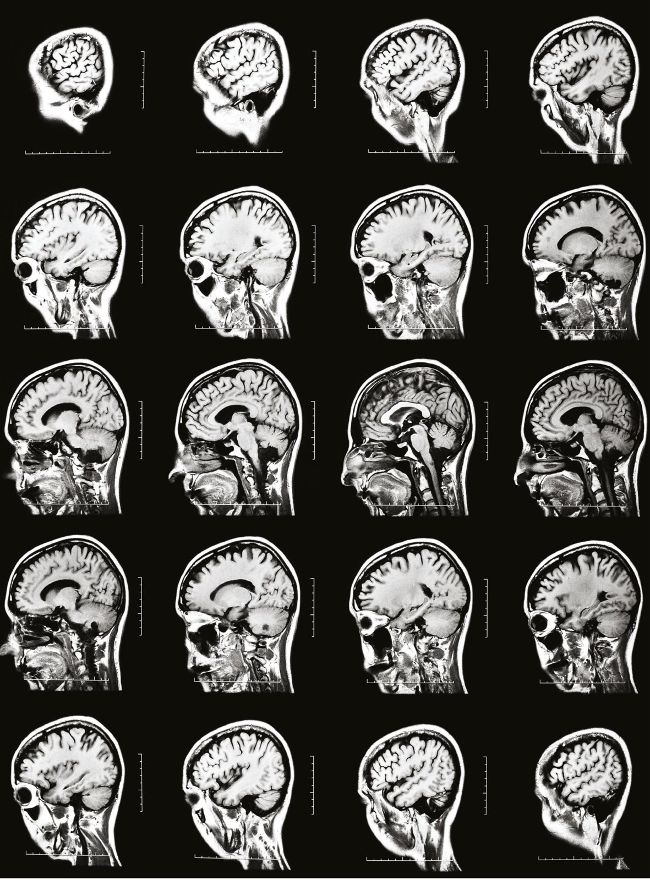

A magnetic view of the mind

Using magnetic resonance imaging (MRI), doctors can take a peek inside our heads. In this series of MRI scans, image slices have been taken vertically from one side of the head to the other, revealing all the cerebral structures in the brain. To capture these, powerful magnetic fields excite atoms in the body, then radio waves are used to detect their movements and convert that information into signals that a computer interprets as an image.